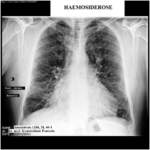

Ὅταν ἕνας βήχας καθίσταται συνεχής, τότε καταστρέφει τὴν καθημερινότητα τοῦ ἀσθενοῦς καὶ αὐτὸς ἦταν ὁ λόγος διὰ τὸν ὁποῖο προσῆλθε στὸ Ἐργαστήριό μας ὁ ἀσθενὴς (εἰκ. 2) ἡλικίας τὸτε (2015) 53 ἐτῶν, χρόνιος καπνιστής καὶ ἐπαγγέλματος ὑπάλληλος γραφείου. Ὅταν προσῆλθε στὸ Ἐργαστήριο, εἶχε βήχα γιὰ πάνω ἀπὸ 10 χρόνια, τὸν ἀπέδιδε δὲ στὸ κάπνισμα, <<τσιγαρόβηχα>> τὸν ἀποκαλοῦσε. Μολονότι παραδέχθηκε ὅτι ὁ βήχας μερικὲς φορὲς ἦταν τόσο ἐπίμονος, σὲ σημεῖο νὰ τὸν ἀπομονώνει κοινωνικά, δημιουργώντας σκέψεις ὅτι πάσχει ἀπὸ κατάθλιψη, «πρέπει νὰ ζεῖς μὲ τὸ γεγονὸς ὅτι κανεὶς δὲν σὲ πιστεύει» εἶπε, ὡστόσο δίσταζε νὰ ἐπισκεφτεῖ γιατρό, ὅμως αὐτὴ τὴν φορά τὸ ἀποτόλμησε, ὅταν τοῦ συνέβη αὐτὸ ποὺ δείχνει ἡ εἰκόνα (εἰκ. 3), δηλ. αἰμόπτυση. Καὶ πάλι ὅμως ἔψαχνε δικαιολογίες, ὅπως ἐπίσκεψη σὲ ὀδοντογιατρὸ τὴν περασμένη ἑβδομάδα… Τέλος ἀνέφερε ὅτι παθαίνει συχνὰ κρυολογήματα μετὰ ρινικοῦ κατάρρου (τὰ διπλάσια σὲ συχνότητα ἀπὸ τὰ ὑπόλοιπα μέλη τῆς οἰκογένειάς του).

Ἡ ἀκτινογραφία θώρακος (εἰκ.2) ἔδειξε στοιχεῖα διαμέσου πνευμονικῆς ἰνώσεως (δικτυοοζώδης σκίαση) ἐντοπιζομένης κυρίως στὰ μέσα καὶ κατώτερα πνευμονικά πεδία ὑπὸ τὴν ἔννοιαν τῆς παρουσίας περιβρογχικῶν καὶ περιαγγειακῶν ἰνώσεων. Τοῦ συνέστησα περαιτέρω κλινικοεργαστηριακὸ ἔλεγχο. Μετὰ τρίμηνο ὁ ἀσθενὴς ἐπανῆλθε προσκομίζοντας τὴν τελικὴ διάγνωση τοῦ Νοσοκομείου Νοσημάτων Θώρακος << Σωτηρία>> καὶ ἡ ὁποῖα ἦταν ἰδιοπαθὴς πνευμονικὴ αἱμοσιδήρωση.Ὁ ἀσθενὴς μᾶς ἐπεσκέφθη ἔκτοτε ἄλλες δύο φορὲς τὸ 2018 (εἰκ.4) καὶ τὸ 2021 (εἰκ. 5), φαινεται δὲ ὅτι ἡ παθολογικὴ ἀκτινολογικὴ εἰκόνα ἐκ τῶν πνευμόνων δὲν ἔχει οὐσιωδῶς μεταβληθεῖ.

Διάγνωση: Βασίζεται στὴν ἀξιολόγηση τοῦ ἱστορικοῦ καὶ τῆς κλινικῆς ἐξετάσεως ἰδία κατὰ τὴν διάρκεια ὀξέων ἐπεισοδίων τῆς νόσου, ὅπου ὁ γιατρὸς στὴν ἀκρόαση μπορεῖ ν’ ἀκούσει ἕνα λεπτὸ κροτάλισμα ἢ κουδούνισμα στὸ τέλος τῆς εἰσπνοῆς. Ὁ ἔλεγχος τῆς πνευμονικῆς λειτουργίας δείχνει περιοριστικὴ ἀναπνευστικὴ διαταραχὴ κατὰ τὴν διάρκεια ἑνός ὀξέος ἐπεισοδίου τῆς νόσου. Ὁ αἱματολογικὸς ἔλεγχος ἀποκαλύπτει σιδηροπενικὴ ἀναιμία. Στὰ ἀκτινολογικὰ εὑρήματα ἑνὸς ὀξέος δυσπνοϊκοῦ ἐπεισοδίου διακρίνει κανεὶς αὔξηση τῆς πνευμονικῆς σκιερότητος στὸ ἐπίπεδο τῶν βρογχιολίων –κυψελίδων ἄνοδο τῶν διαφραγμάτων, σὲ χρόνια δὲ διαδρομὴ τῆς νόσου διακρίνεται δικτυοοζώδης εἰκόνα τοῦ πνευμονικοῦ παρεγχύματος λόγω ἀναπτύξεως διαμέσου πνευμονικῆς ἰνώσεως, διεύρυνση τῶν πνευμονικῶν πυλῶν καὶ μεγαλοκαρδία ἐκ τῆς συνυπαρχούσης πνευμονικῆς ὑπερτάσεως. Ἡ τελικὴ διάγνωση τίθεται μὲ τὴν βρογχοσκόπηση, βρογχοκυψελιδικὴ ἔκπλυση καὶ βιοψία.